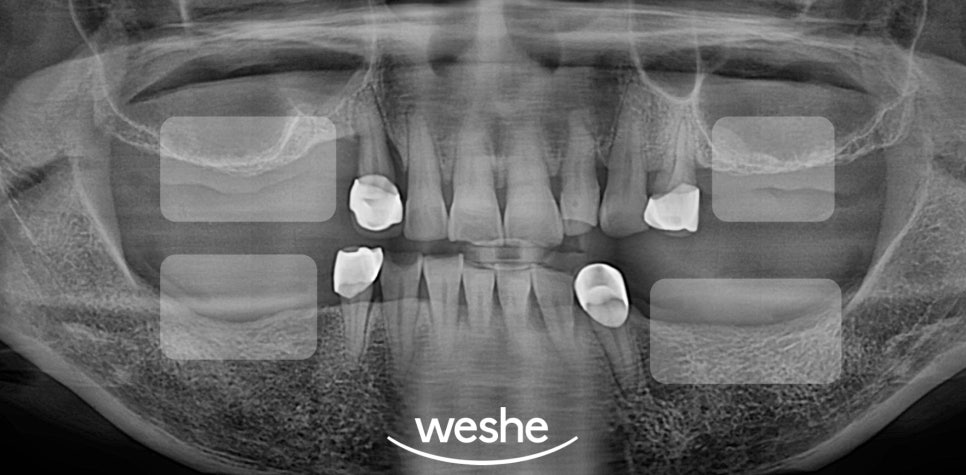

어금니를 잃고 진료를 계획하고 있는데

가용골이 부족하다는 진단을 받으셨나요?

임플란트 를 성공적으로 심으려면

턱뼈에 충분한 양과 품질의 뼈가

남아 있어야 됩니다.

만약 가용골이 부족할 경우에는

골이식술이나 상악동 거상술 등

뼈를 보강하는 추가 치료이 필요합니다.

CT 촬영을 통해

턱뼈의 높이, 두께, 밀도를 정확히

평가해야 됩니다.

이 과정에서 가용골의 정도가

계획과 예후를 결정짓는

요소로 작용합니다.